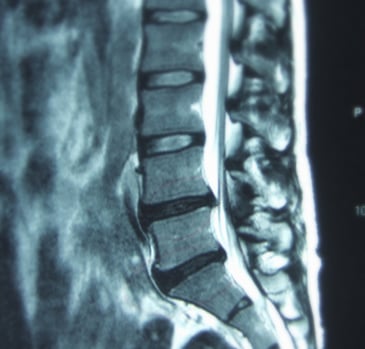

将来的に椎間板ヘルニアや脊柱管狭窄症などの退行変性疾患に苦しむことなく、健康的に歳を重ねていけるようにする。

レントゲン写真や診断書をお持ちの方はぜひご持参下さい。

近年医療機関では、レントゲンのデータをCD-Rで提供が可能になってきておりますので、医療機関にてご確認下さい。理由を聞かれた場合は「自分の経過を記録しておきたいため」と伝えるだけで大丈夫です